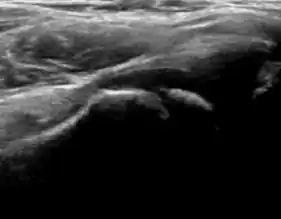

Ultrasound

Ultrasound is the first-choice technique for diagnosis of newborns hip dysplasia. In experienced hands with appropriate technology, ultrasound can also be useful during the first year of life. Some European healthcare systems encourage universal ultrasound screening in neonates between the sixth and eighth weeks. Although it shows higher initial costs caused, it leads to significant reduction in the total number and overall costs of dysplastic hips undergoing operative and nonoperative treatment.[1]

Ultrasound allows categorizing pediatric hips, according to Graf’s criteria, in four main types: normal, immature, and dysplastic (subluxed and dislocated). This classification is based on measurements of the acetabular inclination angle (alpha), cartilage roof angle (beta), and infant age. The femoral head coverage can also be determined by dividing the length of the femoral head covered by the acetabular fossa and the diameter of the femoral head. Its lower normal limits are 47% for boys and 44% for girls (Figure 11).[1]

Figure 11:

-

Useful ultrasound measures in neonatal hip sonography, alpha and beta angles.[1] -

Measurement of femoral head coverage.[1]

During childhood, ultrasound is a quick method to assess hip pain and quite often may be used to avoid use of irradiating techniques, such as radiography or CT. Ultrasound allows evaluation of joint effusion, synovial thickening and neovascularity, the bone/cartilage contour, and the femoral head-neck alignment. Although sonography is extremely sensitive in detecting increased synovial fluid, it is nonspecific and cannot be used with accuracy to determine the type of fluid. Transient synovitis of the hip, despite being the most frequent cause of pain in children between 3 and 10 years, remains a diagnosis of exclusion. It usually shows anechoic fluid, but echogenic fluid can also be found. The effusion is considered pathologic when it is measured at >2 mm in thickness. The differential diagnosis is wide, including osteomyelitis, septic arthritis, primary or metastatic lesions, LCPD, and SCFE. Discrimination from septic arthritis is challenging, often requiring joint aspiration. In septic arthritis, US is able to demonstrate a hip joint effusion, synovial thickening, and cartilage damage, although the appearances are nonspecific.[1]

A step between the head and the physis can be detected in children with SCFE, while abnormalities in the femoral head contour may suggest the presence of LCPD. In both cases, radiographs are mandatory to confirm diagnosis and severity (Figure 12).[1]

Figure 12:

Normal ultrasound appearance of the femoral head-neck junction. -

Joint effusion in transient synovitis of the hip. -

Flattening of the femoral head in a patient with Perthes disease. -

Step in the femoral head-neck junction in a patient with SCFE.

In adults, the most common application for US is to detect tendon or muscle injuries, effusion or synovitis within the hip joint or its adjacent bursae. Joint effusions may be due to many intra-articular processes and this may need another imaging technique to achieve a specific diagnosis.[1]